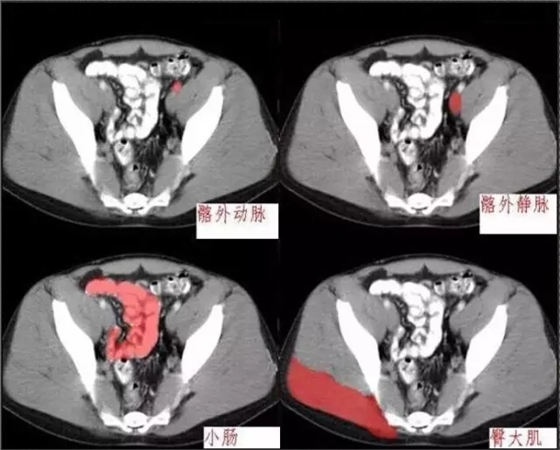

秒懂:腹部 CT 看這篇就夠